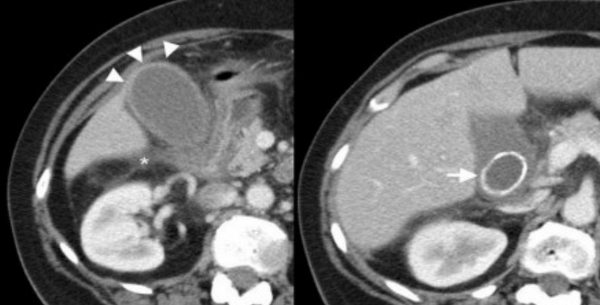

УЗИ и КТ желчного пузыря. Ксантогранулематозный холецистит. Слева на УЗИ визуализируется (помечено стрелками) утолщение стенки желчного пузыря с интрамуральным включением и с камнем в просвете органа. Справа на КТ выявляется утолщение стенки с гиподенсными включениями.

Выше представлено КТ пациента 71 года с ксантогранулематозным холециститом. Постконтрастное КТ. Визуализируется утолщение стенки желчного пузыря с включениями, которые соответствуют абсцессу или фокусам воспаления.

КТ желчного пузыря/Рак желчного пузыря

Наиболее часто встречаемый рак желчного пузыря является карцинома. Карцинома желчного пузыря занимает пятое место по частоте встречаемости среди раков желудочно-кишечного тракта. Чаще его обнаруживают случайно (в 2% случаях) при гистологической проверке после холецистэктомии. Карцинома желчного пузыря выявляется на последних стадиях заболевания так, как себя не проявляет клинически на ранних. Специфических признаков при карциноме желчного пузыря также нет. Рак может поражать желчный пузырь диффузно, целиком стенку или пристеночно. Карцинома желчного пузыря имеет схожую картину с ксантогрануломатозным холециститом, но при постановке диагноза радиологу помогают такие находки:

- Прорастание в соседние органы.

- Вторичная дилатация желчных протоков.

- Метастазирование в печень или лимфатические узлы.

УЗИ (слева) и КТ (справа) желчного пузыря. На УЗИ ярко выраженное утолщение стенки желчного пузыря (указаны белыми стрелками). Множественные камни в просвете желчного пузыря (указано стрелкой). Компьютерная томография с контрастным усилением. На КТ визуализируются утолщение стенки с внутристеночными гиподенсными включениями. На КТ также выявлено, что процесс распространился на печень (указано стрелкой).